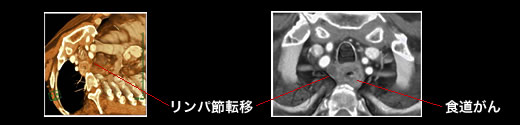

(3) CT 検査

図3. CTによる食道癌の診断

立体表示により、癌の周囲への広がりやリンパ節転移がよくわかります。

CT(コンピューター断層撮影)は、検査ベッドの上に寝た状態で、頚部から腹部までの断層撮影(体の内部の撮影)を行う検査です。内視鏡等で発見された食道癌が周囲の肺、気管、気管支、心臓、大動脈などに及んでいないか、まわりのリンパ腺ははれていないか、肝臓や肺に転移していないかなどを見ることができます。近年の高速高解像度装置により、立体画像を再構築しての診断も可能となりました。